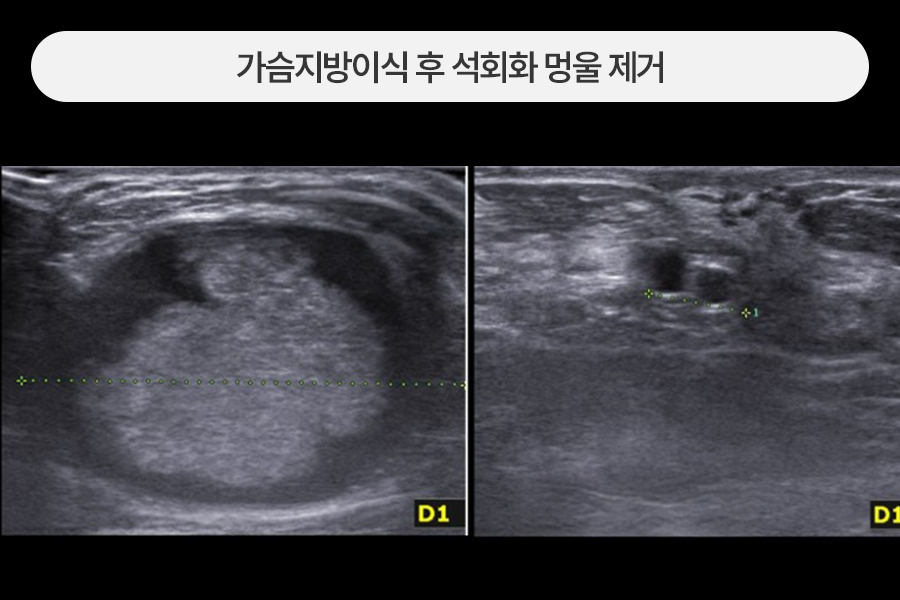

4~5cm 크기의 지방이식멍울 제거

가슴지방이식 후 만져지는 유방멍울이 있어 내원한 분으로

4~5cm 사이즈의 큰 석회화 멍울이 관찰되었습니다.

사이즈가 큰 지방이식 멍울은 급성염증 발생 시 위험도가 높아 최대한 빠른 제거가 필요합니다.

초음파 유도 하에 정상조직을 보존하며 멍울만 안전하게 제거하였습니다.